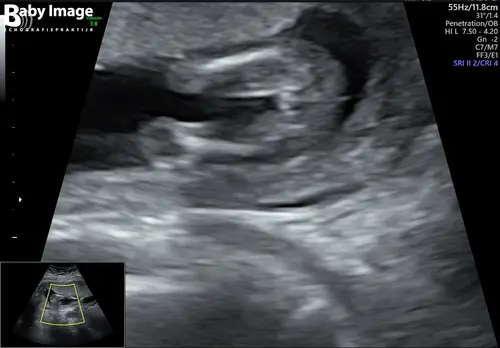

Foto van onderzijde van de baby. Deze week te horen gekregen dat we een meisje krijgen met 15+6, maar ik twijfel als ik dit zo zie. Wat denken jullie?